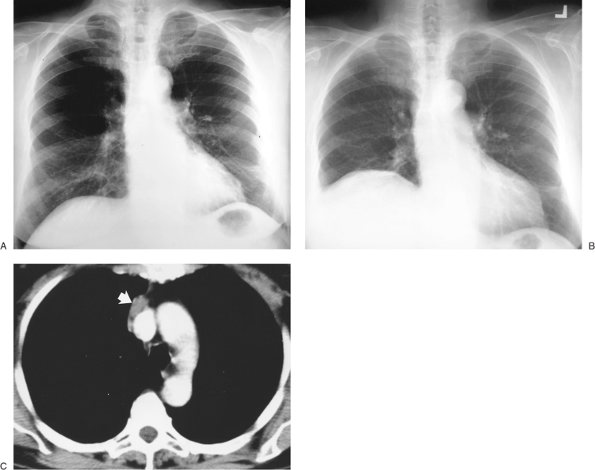

FIGURE 9-44. Bronchogenic carcinoma invading the phrenic nerve. A: PA chest radiograph of a 74-year-old woman shows normal positioning of the hemidiaphragms. B: PA chest radiograph obtained 1 year later shows elevation of the right hemidiaphragm and no evidence of mediastinal mass. C: CT shows a homogeneous soft tissue mass adjacent to the superior vena cava (arrows), which proved to be a bronchogenic adenocarcinoma invading the right phrenic nerve. This case illustrates the significance of new diaphragmatic elevation in an adult, even when no mediastinal mass is seen on the chest radiograph.